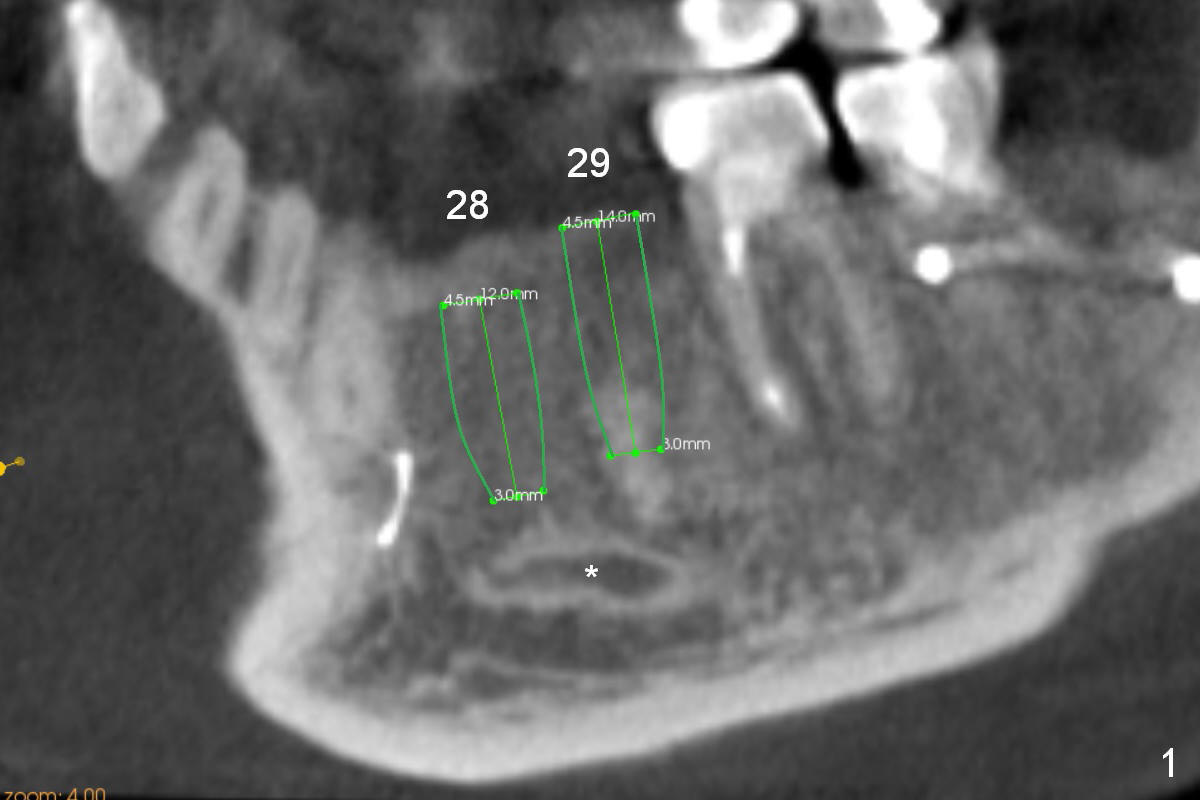

A 39-year-old man had an accident, which caused loss of several teeth 20 years ago. The patient (wearing removable partial dentures) decides to restore #28,29 with implants first (Fig.1 CBCT sagittal section). Coronal section at #28 shows narrow ridge coronally (Fig.2). To place an implant, the pointed ridge top has to be removed about 4.5 mm (Fig.3). Probably due to severe bone resorption post extraction, an angled abutment may be needed as much as 20 degree (Fig.4).

In contrast, the edentulous ridge at the site of #29 is not narrow (Fig.5). A longer implant can be placed (14 mm vs. 12 mm for #28). The patterns of bone resorption at the lower left premolars are quite similar or worse.